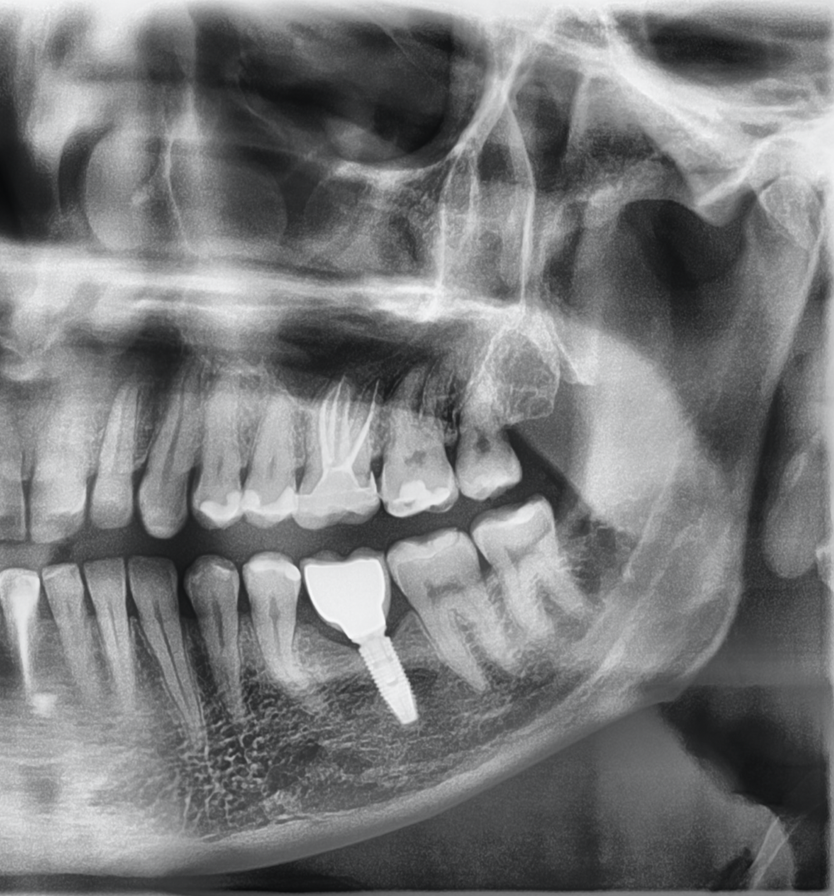

Na kolejnej wizycie wykonano ostateczne płukanie kanałów korzeniowych w następującej sekwencji: 5,25-procentowy NaOCl (Cerkamed) 5 ml na każdy kanał, kwas cytrynowy 40-procentowy (Cerkamed) 3,5 ml na każdy kanał w dwóch cyklach z aktywacją ćwiekiem gutaperkowym o identycznym rozmiarze jak ostatnie użyte narzędzie maszynowe – MDI (manual dynamic irrigation). Kanały osuszono sączkami papierowymi (VDW) i wypełniono metodą kondensacji bocznej zimnej gutaperki z AH Plus Jet (Dentsply De-Trey) (ryc. 5). Ząb zabezpieczono glassjonomerem Riva Self Cure, wykonano kontrolne zdjęcie rentgenowskie (ryc. 6) i odesłano pacjenta do lekarza prowadzącego, który wykonał ostateczną odbudowę protetyczną – endokoronę. Po ukończonym leczeniu kanałowym chirurg stomatologiczny wszczepił pacjentowi implant w miejscu braku zęba 36, który został obciążony po 3 miesiącach (ryc. 7).

Ryc. 7. Pantomogram strony lewej szczęki i żuchwy wykonany około 3 miesiąca od rozpoczęcia leczenia – ząb 26 leczony kanałowo, odbudowany za pomocą endokorony, w miejscu braku zęba 36 – implant z koroną.